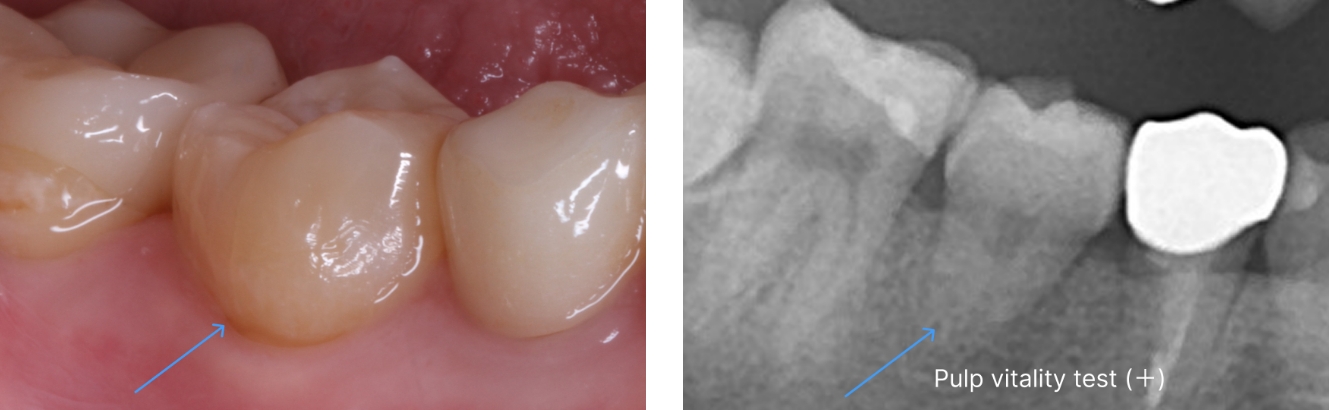

歯牙移植による右下部位の治療例

- 年代、性別 20代・女性

- 来院動機 他院で右下の歯を抜き、インプラントを勧められたが、歯牙移植ができないか相談したいと来院されました。

- 治療内容 右下の残せない歯を抜歯し、ご自身の不要な親知らずを取り出して、右下の抜歯部に移植しました。

- 治療期間 約2週間

- 治療費用 176,000円(税込)

以下の写真の患者様は、移植した歯の歯根根の成長がまだ終わっていなかったため、歯を削ったり神経を取ったりすることなく、移植から11年経った現在も、そのままの状態で自分の歯として元気に機能しています。